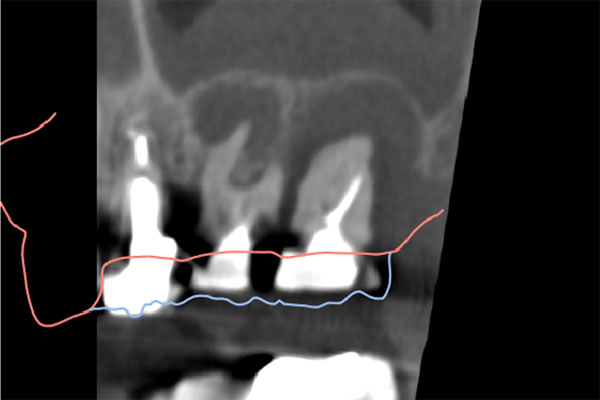

インプラント2本の予定ですので、インプラント同士をほぼ並行に埋入する計画を立てます。神経にインプラントが当たりますと、麻痺が起きたり出血の原因になりますので、

シュミレーション上でもしっかり神経とは距離をおきます。